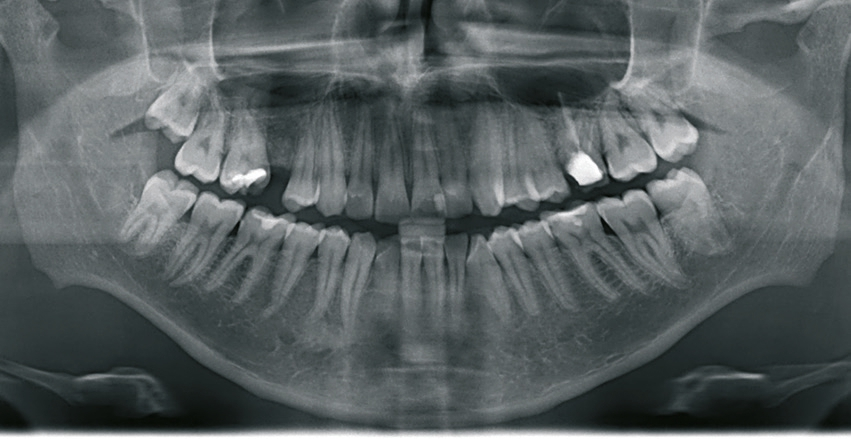

Ein 21-jähriger Patient stellte sich mit einer Perkussionsempfindlichkeit in regio 26 vor. Die klinische Untersuchung zeigte einen tiefzerstörten Zahn 26, dessen gesamte palatinale Wand tief fraktruiert war. Die Frakturgrenze verlief dabei weit unter dem palatinalen Zahnfleischrand (Abb. 1). Nach Erstellung eines Orthopantomogramms und einer radiologischen Einzelzahnbildaufnahme war eine längliche Verschattung am Apex der palatinalen Wurzel des Zahn 26 zu erkennen (Abb. 2), die den Verdacht einer überinstrumentierten Wurzelkanalaufbereitung der palatinalen Wurzel und einer Überstopfung des Füllmaterials bestätigte (Abb. 3). Nach konservierender Theapie wurde die Indikationsstellung für die Extraktion des Zahnes 26 mit einer Sofortimplantation gestellt. Der Periodontal-Screening-Index wies in allen Sextanten Grad 2 auf. Es folgte die Erstellung einer dreidimensionalen Röntgenaufnahme (Orthophos XG 3D, Dentsply Sirona, Bensheim) zur virtuellen Planung der Implantatposition. Die operative Planung erfolgte in der Planungssoftware coDiagnostiX 9.5 (dental wings, Montreal, Kanada) (Abb. 4).